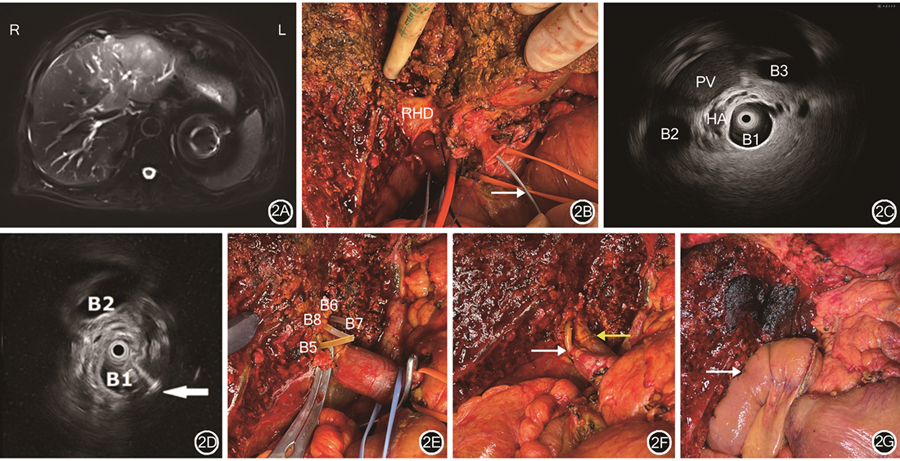

IDUS检查术前可帮助术者判断肿瘤的扩展程度,从而制订手术方案,但尚未有其在术中实时引导的病例报道。笔者团队已在国际上首次将IDUS检查应用于肝门部胆管癌术中引导胆管离断点,并已成功完成6例。示例1:患者女,82岁,发现胆管占位1周入院,有高血压、糖尿病史。术前MRI检查提示肝左叶近肝门部肿瘤。行肝动脉受累肝门部胆管癌扩大根治术,术中切除左三肝,肝右动脉受累切除重建。患者术前影像检查结果及术中IDUS检查图像显示见图2。

注:IDUS为胆管腔内超声;RHD为右肝管;PV为门静脉;HA为肝动脉;B1为IDUS探头所在右肝段胆管;B2、B3为正常右肝段胆管;B5为肝Ⅴ段胆管;B6、B7为肝Ⅵ、Ⅶ段胆管;B8为肝Ⅷ段胆管